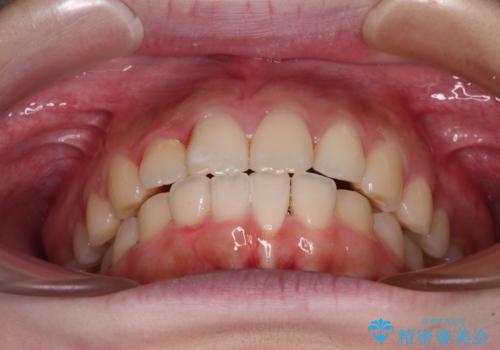

前歯のデコボコをインビザラインできれいに整える

- 前歯のデコボコと上下の隙間を気にして来院された患者様です。

前歯の捻れを改善するとともに、口元が少しでも引っ込むように治療計画を立て、仕上げることができました。

長時間の装着や、定期的な来院がままならず、想定よりも長期間の治療となってしまいました。